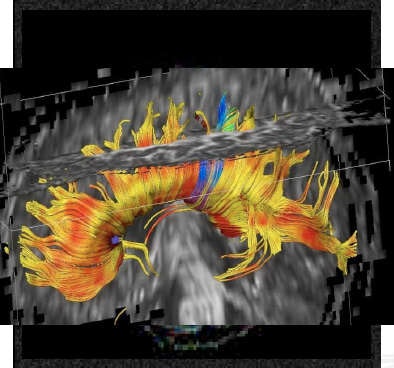

Besides understanding brain development, the radiologist must look for imaging patterns. Heterotopia is a migration disorder that happens when the neuronal stem cells migrate from the germinal matrix zone to the cortical surface. At some point along the way, they get left behind and don't arrive where they should. In answer to the question posed by a delegate of how to differentiate heterotopia from other white-matter abnormalities, the key factors given were the signal isointensity to cortex and the location along radial migration pathways.

Four basic sequences will answer most of the questions aimed at ruling out common malformations in children with developmental delay, Ertl-Wagner told delegates. These are T2-weighted axial sequence, T2-weighted sagittal sequence, FLAIR sequences, and T1-weighted inversion-recovery sequences. Motion correction sequences can be especially helpful when imaging children. In addition, 3D sequences can aid in detecting small abnormalities, in patients with epilepsy, for example.

The usefulness of additional sequences depends on the disorder being imaged. For patients with epilepsy, either adult or child, it may be appropriate to carry out very thin section imaging of the entire brain, such as 3D sequences, with reconstructions through the hippocampi, for example.